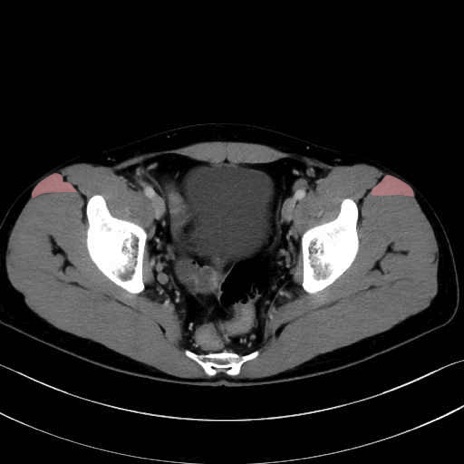

大腿筋膜張筋 (Tensor fasciae latae)